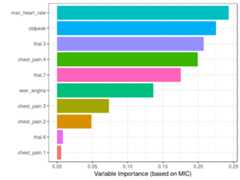

1.2.10 Correlation analysis based on information theory

Based on MIC measure, mine function can receive the index of the column to predict (or to get all the correlations against only one variable).

# Getting the index of the variable to# predict: has_heart_diseasetarget="has_heart_disease"index_target=grep(target,colnames(heart_disease_4))# master takes the index column number to calculate all# the correlationsmic_predictive=mine(heart_disease_4,master = index_target)$MIC# creating the data frame containing the results,# ordering descently by its correlation and excluding# the correlation of target vs itselfdf_predictive =data.frame(variable=rownames(mic_predictive),mic=mic_predictive[,1],stringsAsFactors = F)%>%arrange(-mic)%>%filter(variable!=target)# creating a colorful plot showing importance variable# based on MIC measureggplot(df_predictive,aes(x=reorder(variable, mic),y=mic,fill=variable) )+geom_bar(stat='identity')+coord_flip()+theme_bw()+xlab("")+ylab("Variable Importance (based on MIC)")+guides(fill=FALSE)

Figure 1.18: Correlation using information theory

Although it is recommended to run correlations among all variables in order to exclude correlated input features.